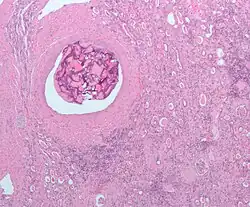

Micrograph of embolic material in the artery of a kidney. The kidney was surgically removed because of cancer. H&E stain. |